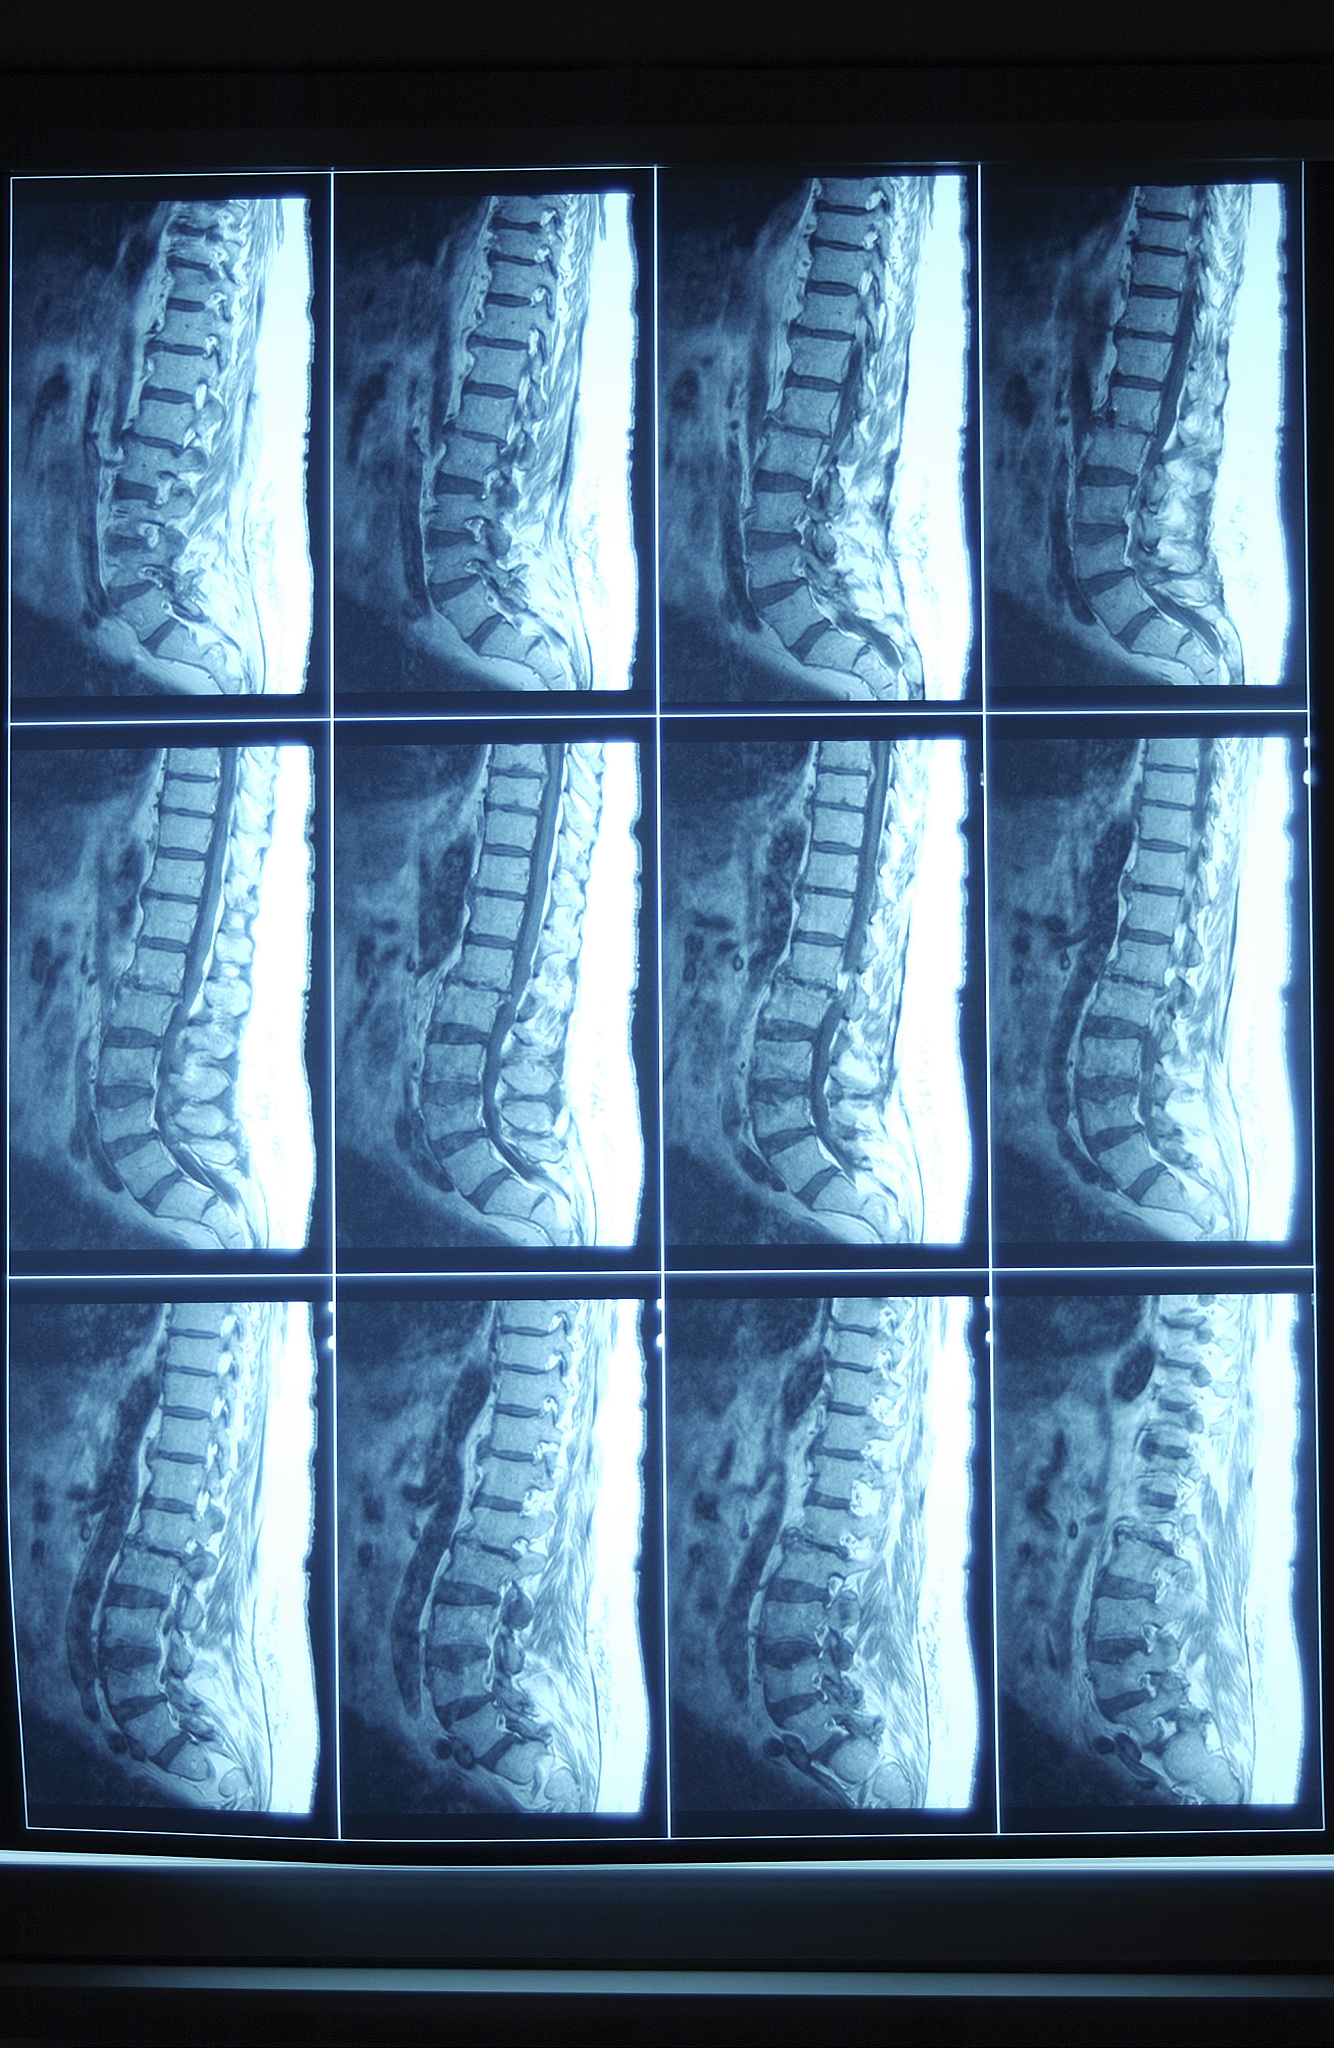

2. 脊柱退行性疾病的治疗方法和预防措施 脊柱退行性疾病是老年人的常见病,本文将介绍其治疗方法,以及预防措施,帮助患者减轻症状,改善生活质量。

8. 颈椎病的预防和治疗 颈椎病是现代人常见病,本文将介绍颈椎病的预防方法以及治疗方案。